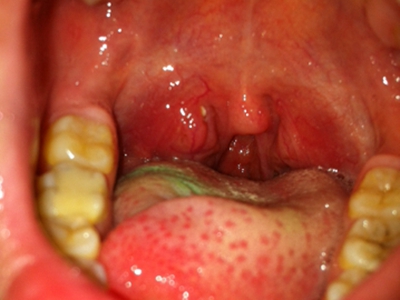

疱疹性咽炎症状图片

疱疹性咽炎潜伏期3-10天,多以突发高热开始,可升至39℃-41℃,伴头痛、咽部不适、肌痛等,婴幼儿常呕吐、拒食,甚至发生高热惊厥;年长儿童常见严重的咽痛、吞咽困难、四肢肌痛、厌食乏力等,持续4-5天后,咽部出现灰白色小丘疹,24小时内发展为水疱和溃疡,其周围绕以直径1-5mm的红晕为特征性的病变,皮损常现于扁桃体前柱、软腭缘和悬雍垂,经1-5天溃疡愈合,一般3天内退热,7日内症状消失。一般疱疹性咽炎往往都伴有牙龈出血、口腔异味,还可伴有颌下淋巴结肿大,但很少波及口腔外部的皮肤。